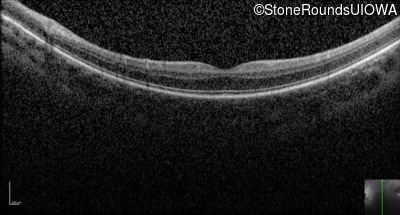

Optical Coherence Tomography - Left - 20/80 -2

Exemplar / OCT Stack

OCT Stack